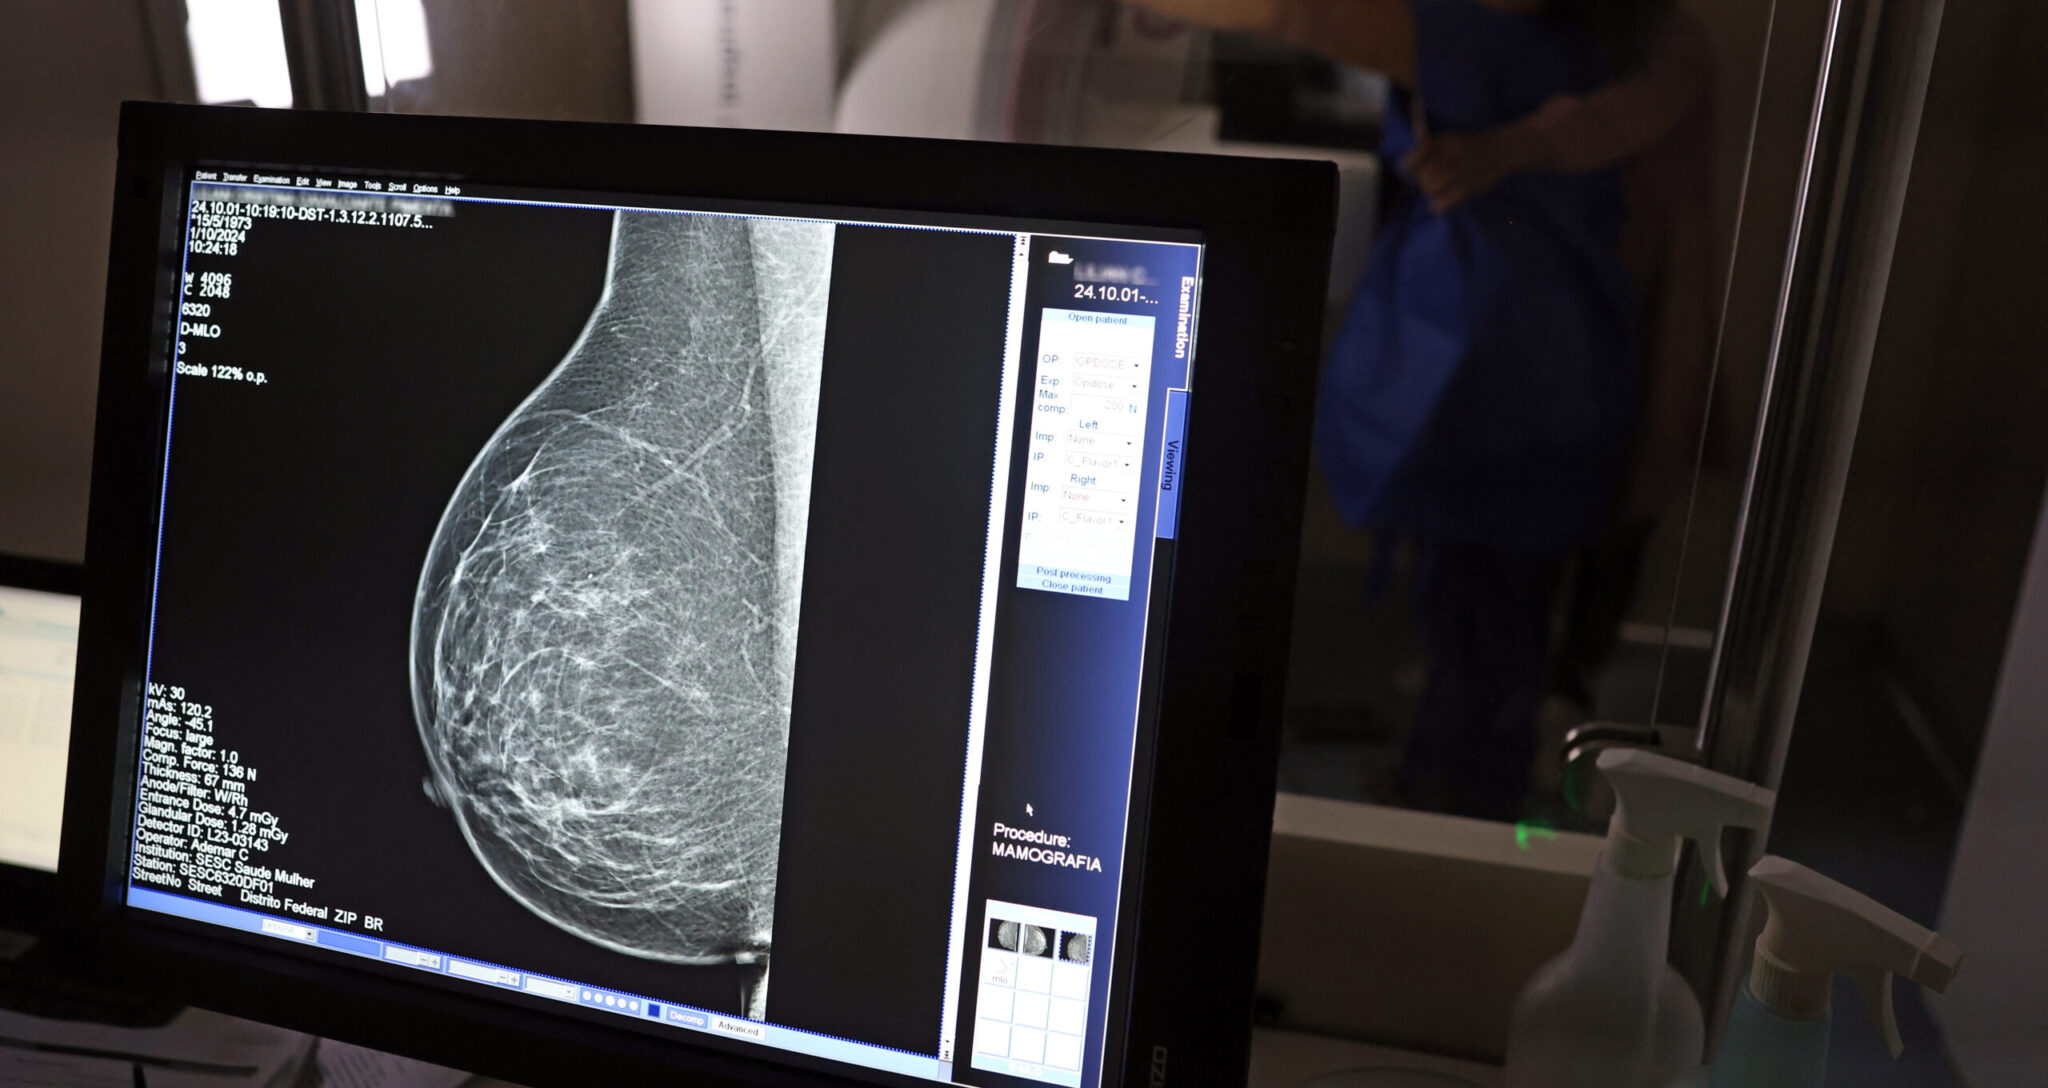

Com mais de 57 mil mamografias realizadas em 2025, o Piauí ampliou significativamente o acesso ao diagnóstico precoce do câncer de mama, especialmente entre mulheres a partir dos 40 anos. Como parte das ações de reforço ao tratamento, o estado recebeu, na quinta-feira (23), uma remessa com 224 unidades do medicamento Trastuzumabe Entansina, recém-incorporado ao Sistema Único de Saúde (SUS) para casos avançados da doença.

A rede estadual conta com 43 mamógrafos fixos e o serviço itinerante dos Caminhões da Mamografia, que percorrem os municípios levando o exame a quem mais precisa. O foco principal tem sido nas mulheres entre 40 e 49 anos, faixa etária que passou a ser atendida sob demanda, conforme nova orientação do Ministério da Saúde.

“Outubro Rosa é um mês para toda sociedade se concentrar na proteção às nossas mulheres, sobretudo na prevenção do câncer de mama. Por isso estamos descentralizando, não apenas com mutirões, mas com salas permanentes de mamografia. É o caso da Central de Diagnóstico de Valença, que agora atende toda a região sem fila de espera. Viva as mulheres, viva o Outubro Rosa!”, declarou o governador durante visita ao hospital da cidade.

A técnica em radiologia Ana Vitória atua na Central de Diagnóstico de Valença e confirma o impacto direto na vida da população. “Antes o exame só era disponibilizado em clínica particular. Agora, mulheres de toda a região vêm aqui, fazem o agendamento e realizam o exame. Atendemos mulheres a partir dos 40 anos, sem fila, com estrutura pública. Isso melhorou muito a vida das pessoas”, afirma.

O ministro da Saúde, Alexandre Padilha, reforçou a importância da mobilização nacional. “Estamos orientando que mulheres de 50 a 74 anos façam mamografia pelo menos a cada dois anos, com rastreamento ativo pelas equipes de saúde da família. E se uma mulher a partir dos 40 anos quiser fazer o exame, o profissional deve garantir o acesso. Além disso, atualizamos os medicamentos para tratamento, com os mais modernos disponíveis no SUS, aumentando a chance de sobrevida”, destacou.